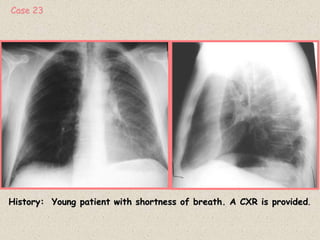

History: Young patient with shortness of breath. A CXR is provided.

Case 23

See slide 61 for detailed explanation of lobar collapse